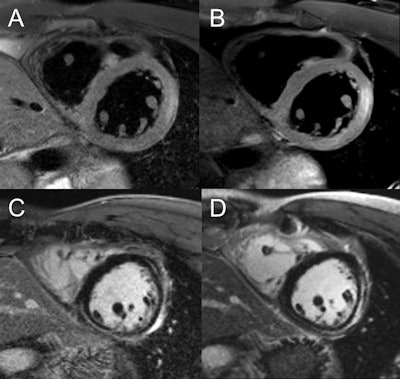

Image comparison in assessment of myocarditis in patient with initial examination performed at 1.5 tesla (A,C) and follow-up at 3 tesla (B,D). T2-weighted spectral attenuated inversion recovery (SPAIR) for assessment of edema (A,B), as well as late gadolinium enhancement imaging (C,D), show improved image quality with higher spatial resolution at 3 tesla. Images courtesy of Dr. Bernd Wintersperger.The quality of myocardial first-pass perfusion imaging is enhanced by using 3 tesla, and assessment of myocardial ischemia can improve as a result of the change. Also, contrast-enhanced MR angiography (MRA) benefits from increased field strength, and this brings gains for patients with aortic or pulmonary vasculature diseases. For both applications, tissue contrast is higher and high-resolution imaging can be pushed beyond 1.5 tesla capabilities.